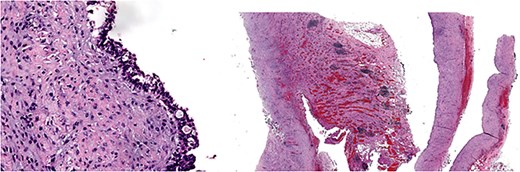

Give the symptomatology and anatomical impact, GDC resection was prioritized. Planned laparoscopic wedge resection was converted to upper midline laparotomy due to dense adhesions. The GDC, ~10 × 10 cm, originated from the posterior stomach wall with no luminal communication. The cyst ruptured during resection; the stomach wall was reinforced with sutures (Fig. 3). Histopathology confirmed GDC, showing gastric layers and underlying smooth muscle bundles, without atypia (Fig. 4). Post-operatively, the patient developed postprandial vomiting and abdominal pain and were attributed to small bowel adhesions, which resolved with conservative management. The patient achieved full recovery thereafter.

Histology image: Sections show a non-communicating cystic structure with a well-defined smooth muscle layer. No atypia or malignancy. The epithelium is flattened without atypia and occasional mucin-producing cells. Focal granulation tissue seen within smooth muscle bundles.

Although our specimen lacked well-defined gastric glands, histopathology supported a diagnosis of GDC. Several papers have also elucidated the histological heterogeneity of GDC [2]. The epithelial flattening and granulation are likely reflecting chronic inflammatory reactions.